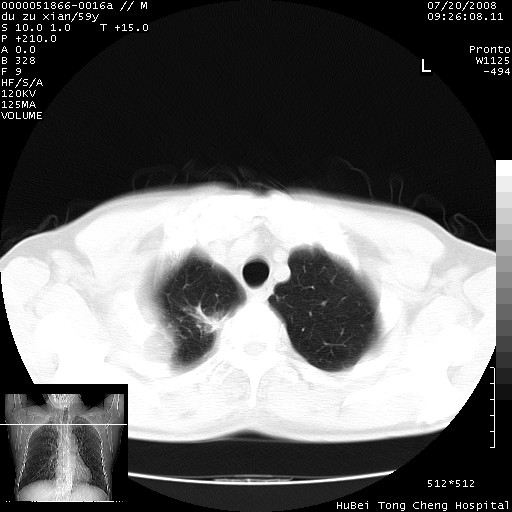

以下是引用宇宙ct在2008-8-25 23:21:00的发言:[br]右肺周围性肺癌并肋骨转移,纵隔淋巴结转移。

以下是引用zsl6918在2008-8-25 22:40:00的发言:[br]右肺周围性肺癌并肋骨转移,纵隔淋巴结转移。

以下是引用zy_zj在2008-8-26 15:24:00的发言:[br]单从病变本身,我倾向良性炎性病变,但肋骨转移了,所以说是考虑右肺周围性肺癌并肋骨、纵隔淋巴结转移可能性大。